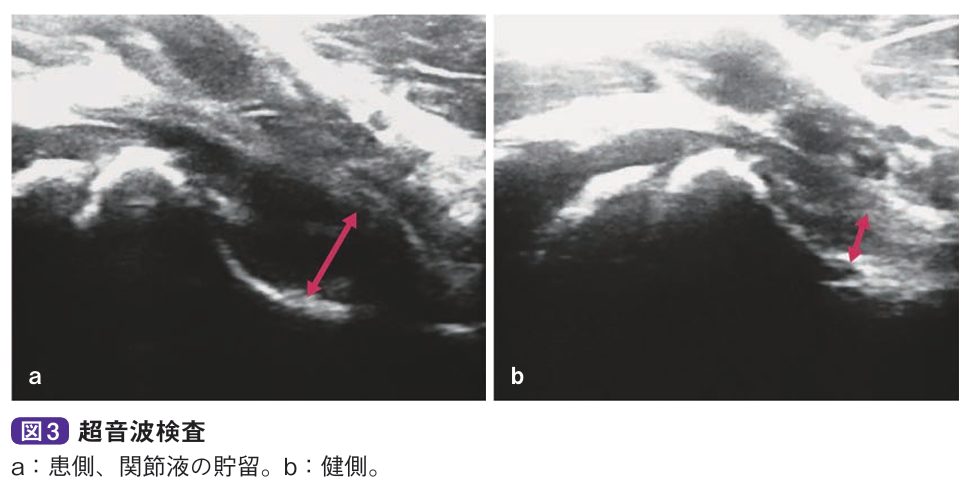

診察とレントゲン、エコーなどで診断します。関節可動域は軽~中等度と制限され、とくに屈曲位で内旋が制限されます。微熱を認めることがありますが、通常、血液所見は正常値を示します。単純X線像では関節液の貯留により関節包陰影の膨隆、関節裂れつ隙げきの開大、骨頭の外方化などを認めますが、骨陰影に異常を認めません。超音波検査やMRI検査で関節液貯留が明らかとなります。